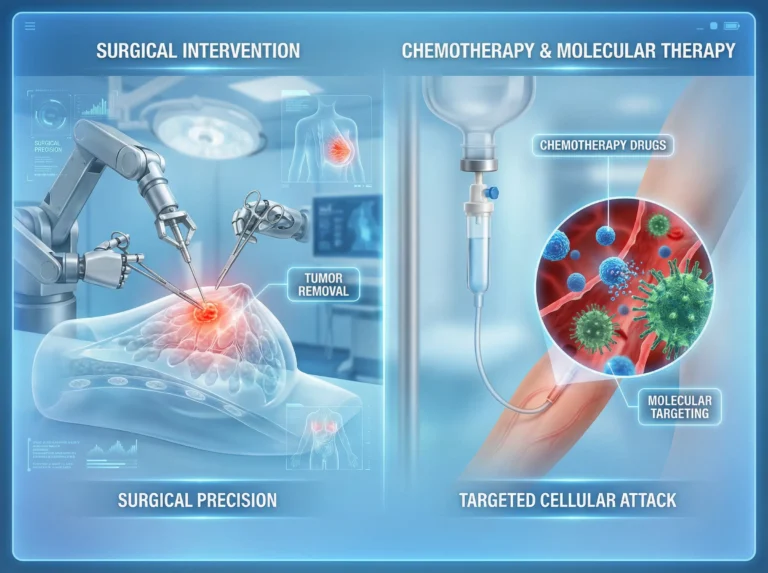

Essentials Advanced Breast cancer treatment in Mira Road. Breast cancer remains one of the most pressing health challenges worldwide, and surgical intervention…

Introduction Minimally Invasive Cancer Surgery in Mira Road. Let’s understand, Cancer treatment has evolved dramatically over the past few decades, with surgical…

Why Choose Laparoscopic Cancer Surgery in Mira Road for Cancer Treatment Cancer treatment has evolved significantly over the past few decades, with…

Introduction Hearing the words breast cancer can feel overwhelming. If you’re here, you or someone close to you might be facing difficult decisions. One…

If you or someone you love is facing breast cancer, the idea of surgery can feel overwhelming. In this guide, we’ll walk…